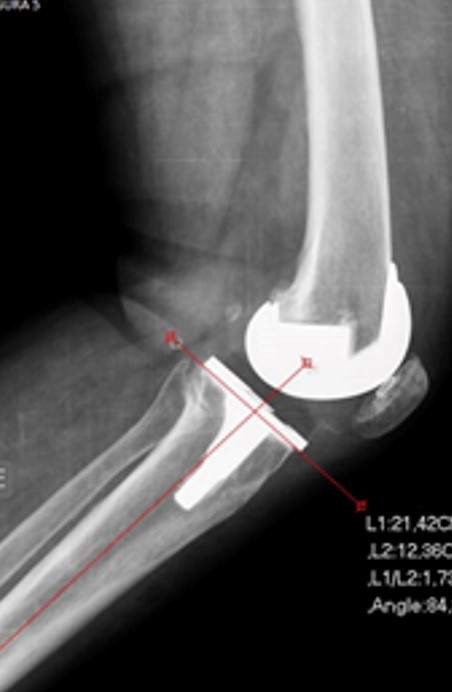

Foram analisadas as imagens de radiografias do joelho operado obtidas no pós-operatório imediato em ântero-posterior (AP) e perfil, bem como as imagens em AP e perfil do joelho com carga, realizadas com 3 meses de seguimento clínico, conforme protocolo da instituição. Os exames de imagem foram avaliados por um único observador membro do grupo de cirurgia do joelho. A análise radiográfica foi realizada de forma cega sem identificação do paciente. O software utilizado para o estudo foi o mDicomViewer 3.0 (Microdata, RJ-Brasil, 2007). O alinhamento coronal e sagital foram determinados pela medição de cinco ângulos radiográficos.15 O primeiro foi avaliado na radiografia em AP. Essa análise foi feita através de um ângulo formado pela superfície distal do componente femoral e o eixo da diáfise do fémur, além de um segundo ângulo formado entre o planalto tibial e o eixo da diáfise da tíbia (figura 2 A-B). Além disso, analisamos o ângulo tibio-femoral formado entre os eixos anatómicos do fémur e da tíbia (figura 3). A avaliação do alinhamento no plano sagital foi realizada através da radiografia em perfil, determinando-se o ângulo entre a parte mais distal da superfície de fixação femoral e o eixo da diáfise do fêmur (figura 4). De forma similar, a avaliação do alinhamento da tíbia nessa incidência corresponde ao ângulo entre o planalto tibial e o eixo da diáfise da tíbia (figura 5). O alinhamento patelofemoral não foi avaliado.